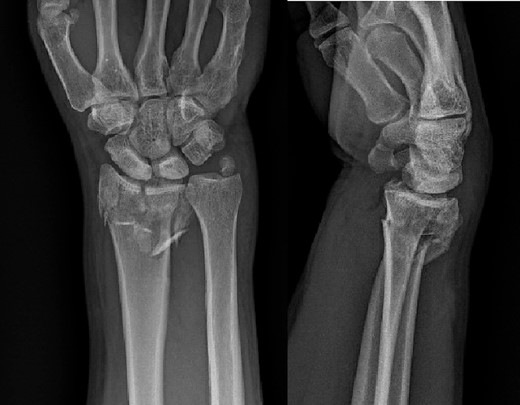

A 43-year-old man presented to the emergency department after falling ~5 ft from a ladder onto his outstretched right hand. He reported immediate pain and inability to bear weight through his right wrist. On physical examination, there was right wrist swelling and limited range of motion (ROM). The skin was intact, and neurovascular exam was normal. The patient had no other injuries and no pertinent medical history. Initial radiographic imaging confirmed a comminuted intra-articular distal radius fracture with dorsal displacement along with an ulnar styloid fracture (Fig. 1). The patient was placed in a sugar-tong splint and followed-up in clinic a week later with surgical treatment planned (Fig. 2).

Preoperative radiological assessment of the patient with postero-anterior (PA) and lateral views of the right wrist.